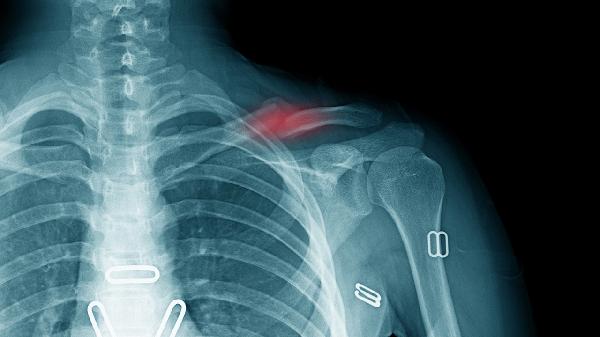

鎖骨骨折后可通過高蛋白食物、富含鈣質食物、維生素D補充、膠原蛋白攝入、鋅元素補充等方式促進骨骼愈合。鎖骨骨折的恢復與營養(yǎng)支持密切相關,合理的飲食結構能加速骨痂形成。

鎖骨骨折恢復期需建立均衡膳食模式,除上述重點營養(yǎng)素外,還應保證新鮮蔬果攝入以提供抗氧化物質。避免高鹽、高糖及含磷碳酸飲料影響鈣代謝,戒煙限酒以防血管收縮阻礙愈合。餐后適當活動促進消化吸收,但需避免患側負重。定期復查X線觀察骨痂生長情況,若出現(xiàn)愈合延遲需在醫(yī)生指導下調(diào)整營養(yǎng)方案。睡眠時保持患肢功能位,配合醫(yī)囑進行漸進式康復訓練,營養(yǎng)與運動結合可顯著提升恢復效果。